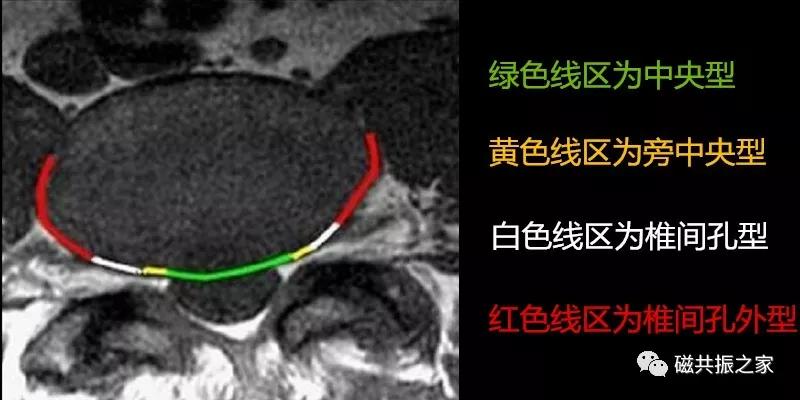

95%的椎间盘突出为中央型或旁中央型,5%的椎间盘突出为椎间孔型和椎间孔外型(图片来自网络),拓展阅读椎间盘突出表现。